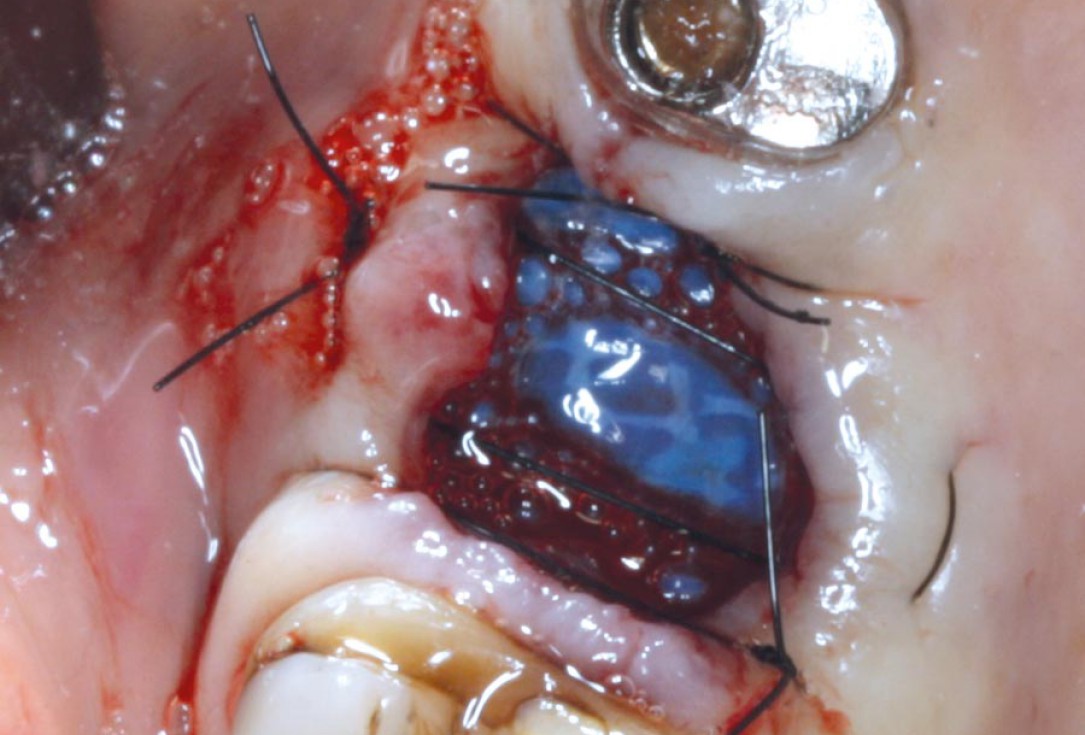

04/07 - Extraction socket covered with permamem®. The membrane is placed under the soft tissue.Socket preservation with permamem® - Dr. M. Turco

05/07 - Stabilization of the extraction site and immobilization of the membrane with cross sutures.Socket preservation with permamem® - Dr. M. Turco